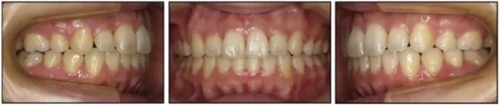

五、治療結(jié)果

治療后數(shù)據(jù)提示治療目標(biāo)達(dá)成。面相結(jié)果提示微笑及側(cè)貌得到改善(圖6)。達(dá)到了安氏I類尖牙關(guān)系和安氏II類磨牙關(guān)系,形成尖牙保護(hù)合。牙齒中線無偏斜,達(dá)到理想的覆合覆蓋,Spee曲線得到整平。